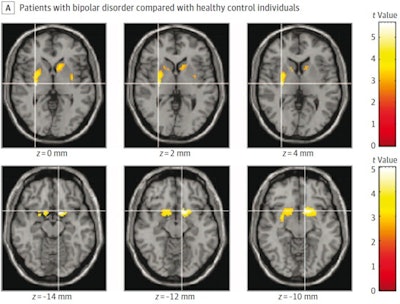

To explore the connection, Yatham and colleagues recruited patients with bipolar disorder from a care referral center for mood disorders in Vancouver. The research included 26 patients with bipolar disorder (9 with current mania and 17 with recently remitted mania) and 21 matched healthy individuals. Study participants underwent PET imaging with the radiotracer carbon-11 d-threo-methylphenidate, which binds to DAT and reveals its density on the scans in areas of the brain involved in emotional and behavioral functions.

Results showed that DAT radiotracer binding was significantly lower in patients with bipolar disorder in the right putamen and nucleus accumbens areas of the brain, as well as the left putamen and caudate. The reduction in binding was more extensive and pronounced in patients with current mania, while patients with recently remitted mania had lower binding in the left striatum but not the right, according to the findings.